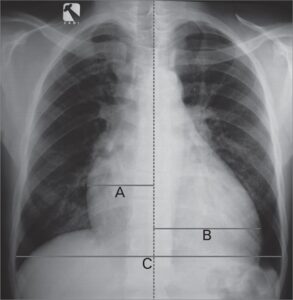

O aumento do átrio direito é uma condição onde a câmara superior direita do coração se torna...

O aumento do ventrículo esquerdo é definido como um aumento da massa do ventrículo, que pode ser...

A hipertrofia ventricular direita é um aumento anormal da massa muscular do ventrículo direito, geralmente como resposta...

Mediastino é um espaço no meio do tórax entre a pleura de cada um dos pulmões e...